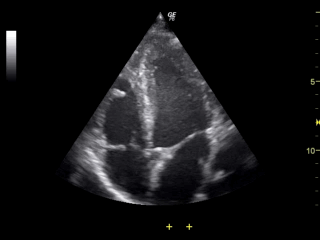

Ultrasonografia, USG, echo

Ultrasound_of_human_heart_apical_4-cahmber_view.gifNajtańsze, najprostsze i najmniej inwazyjne badanie. Na animacji bijące serce z widoczną pracą zastawek.

Zasada działania: wysyłamy bardzo krótkie impulsy dźwiękowe i rejestrujemy sygnał powrotny. Fala dźwiękowa odbija się na granicy ośrodków o różnych impedancjach akustycznych - czyli w naszym przypadku różnych tkankach. Im większa różnica impedancji (np. na granicy kości, albo pęcherzyka powietrza w jelitach), tym więcej zostaje odbite i mamy większy sygnał (jasny obraz). Co za tym idzie, wszystko co znajduje się za takim obiektem będzie dawało mniejszy sygnał.

Co widzimy: granice i jednorodność tkanek, głównie tkanek miękkich. Bardzo ładnie widać np ścięgna, niejednorodności (guzy) wewnątrz narządów, czy kształt wątroby, nerek. No i oczywiście płód. A i jeszcze jest efekt Dopplera - jeśli aparat poza intensywnością mierzy też częstotliwość fali odbitej, to możemy zmierzyć prędkość przepływu np. krwi w naczyniach.

Ograniczenia i zagrożenia: słabo widać wszystko za kośćmi - przy USG płuc czy serca lekarz celuje między żebra, USG mózgu jest możliwe wyłącznie u noworodków z niezarośniętym ciemieniem. Do tego jest niewielkie ryzyko kawitacji - przejścia niewielkiego obszaru z fazy ciekłej w gazową, po którym następuje implozja powstałego bąbla powietrza, co z kolei prowadzi do powstania szkodliwych wolnych rodników. Dla ograniczenia ryzyka powinno się unikać trzymania głowicy nieruchomo - aparaty mają funkcję stopklatki, jeśli lekarz chce coś zmierzyć lub zanalizować.